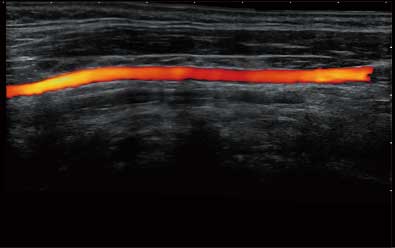

通过对组织运动信息、血流信号及背景噪声进行准确智能的阈值判定,高效提取出微弱血流信号,获得高灵敏度和空间分辨率的血流图像,为临床提供更加真实和丰富的诊断信息。